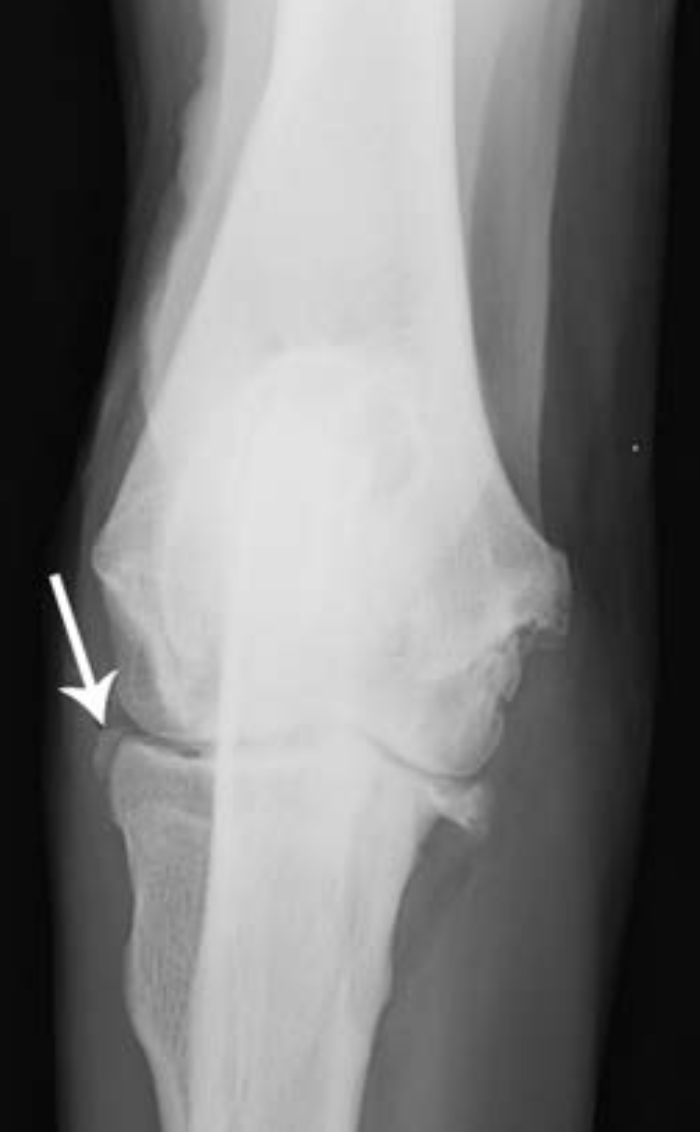

4-year-old Rottweiler

large separate medial coronoid fragment superimposed on the cranial radius (arrowed). Osteophytic reactions are seen on the cranial margins of the joint and on the anconeal process and subtrochlear sclerosis.